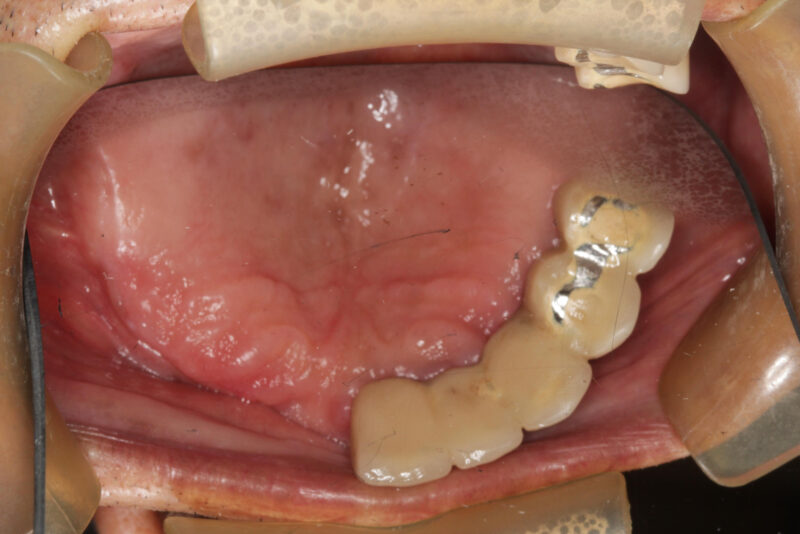

• Placed an implant and healing abutment and patient came with overgrown tissue on lingual which is not soft or hard but a bump. At first I thought it was an ill-fitting interim denture and adjusted. Also placed a soft liner. She came back 2 weeks later still there. So I placed a taller healing abutment and adjusted her existing denture to not…

Read more

• From the picture, it looks like some decent quality tissue that has built up over time. When you finish your new prosthesis and have proper tissue pressure everywhere, it might settle down slightly, but at this point, I would just leave it as it’s better to have that type of tissue than oral mucosa up against your locators. It looks like…

• Have you tried adjusting the tissue at all? You could just use a 15 blade and trim it down a bit. It’s not the end of the world to have the tissue bulging like that but it can be a nuisance